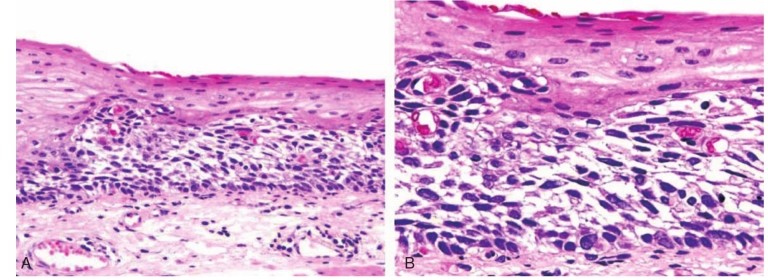

食管腺癌(OAC)是一种起源于食管黏膜腺细胞的肿瘤生长。

慢性GORD可能发展为巴雷特食管(BO),这是已知的OAC的前兆,反流症状虽然很常见,但也是OAC发展的危险因素。

更多的证据围绕获得的遗传和表观遗传现象可能影响化生发育不良腺癌序列,丰富的研究检索了各种因素的影响如染色体失衡,增殖紊乱,凋亡,对抗生长信号的反应丧失。